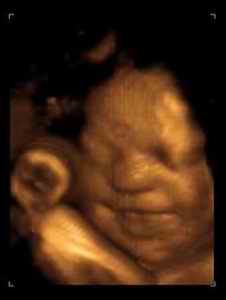

其实,关于胎宝宝在肚子里微笑,类似的报道并不少见,很多妈妈反馈过做四维时看到宝宝笑的样子,国外媒体也经常报道类似的新闻。

2003年,英国《卫报》报道,科学家用4D超声波成像系统拍到了26周宝宝微笑的图片。

2018年,英国《每日邮报》报道,一对夫妇在做四维彩超时发现宝宝咧嘴微笑,让父母感到喜出望外。

见诸各大网站的3D胎儿图像,也展示了胎儿在19周时微笑的模样,栩栩如生,惹人喜爱。

从这里看出,在做四维彩超的时候很容易捕捉到胎儿的微笑,这时不要觉得奇怪,这是胎儿正常的生理反应。